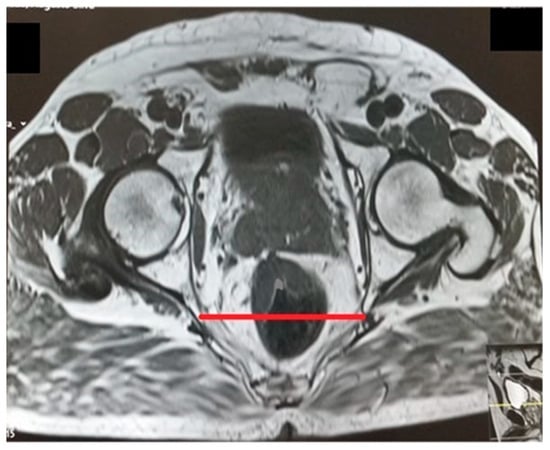

The pelvic measurements on MRI (Figure 2, Figure 3, Figure 4, Figure 5, Figure 6 and Figure 7) were carried out by the author, and to maintain the reproducibility of the results, measurements were taken, whenever possible, at the same anatomical levels.

Figure 4.

Interspinous distance.